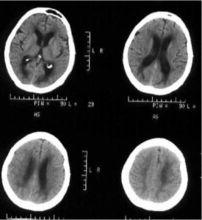

脱髓鞘病变ct,脑白质脱髓鞘CT

脑白质脱髓鞘

脑白质脱髓鞘CT

脱髓鞘

脱髓鞘病变图片

脱髓鞘图片

脑白质脱髓鞘病变

脱髓鞘核磁共振图

脑白质脱髓鞘图片